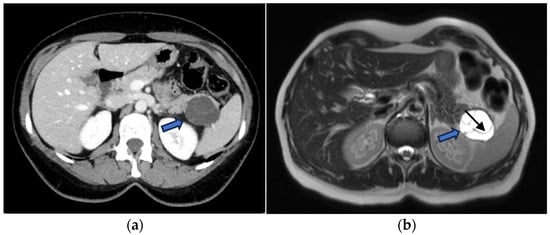

Pancreatic Cystic Lesions: From Basic Knowledge to Recent Guidelines

by Ginevra Danti, Ludovica Scalzone, Lavinia Mattolini, Matilde Anichini, Francesca Treballi, Linda Calistri, Diletta Cozzi and Vittorio Miele

Pancreatic cystic lesions (PCLs) are increasingly detected due to widespread use of cross-sectional imaging. They encompass a heterogeneous group of lesions, ranging from benign pseudocysts and serous cystic neoplasms (SCNs) to premalignant mucinous cystic neoplasms (MCNs) and intraductal papillary mucinous neoplasms (IPMNs), as [...] Read more.

Pancreatic cystic lesions (PCLs) are increasingly detected due to widespread use of cross-sectional imaging. They encompass a heterogeneous group of lesions, ranging from benign pseudocysts and serous cystic neoplasms (SCNs) to premalignant mucinous cystic neoplasms (MCNs) and intraductal papillary mucinous neoplasms (IPMNs), as well as rare malignant entities such as solid pseudopapillary epithelial neoplasm (SPENs) and cystic pancreatic neuroendocrine tumors (cystic PanNETs). Management of PCLs depends on their malignant potential; therefore, an accurate classification is essential for optimizing treatment. This narrative review summarizes current knowledge on the epidemiology, imaging characteristics, diagnosis, and management of PCLs, highlighting the role of CT, MRI, MRCP, and endoscopic ultrasound. Recent advances in radiomics for lesion characterization and risk stratification, particularly in IPMNs, are discussed. Full article

Show Figures

Figure 1